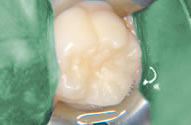

シーラント

生えたての永久歯は、気を付けて歯ブラシをしていても、むし歯になりやすいです。理由は、歯の溝がとても深いからです。

その溝を埋めることで、汚れがたまりにくく、むし歯予防に効果があるのがシーラントです。

歯を削らずに、溝にフッ素が配合されたセメントを流し込みます。